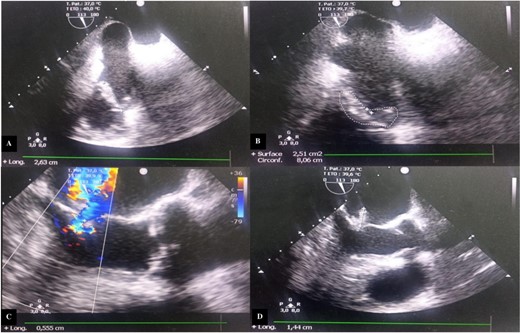

We performed an annular suture, followed by suturing the papillary muscles into the right ventricle: the anterior papillary muscle to the interventricular septum and the posterior papillary muscle to the posterior tricuspid papillary muscle. The repair was consolidated with a tricuspid annuloplasty ring (size 32; Carpentier-Edwards) (Fig. 3). Cultures of the resected segments were negative. Post-operative follow-up was uneventful, and echocardiographic follow-up at discharge showed no residual tricuspid regurgitation or stenosis (Fig. 4).

Intraoperative images. (A) Vegetations on the anterior tricuspid leaflet. (B) Valvular suture of the mitral autograft to the native tricuspid annulus. (C) Suture of the anterior papillary muscle of the mitral autograft to the interventricular septum. (D) Tricuspid annuloplasty ring with no residual regurgitation at serum testing.